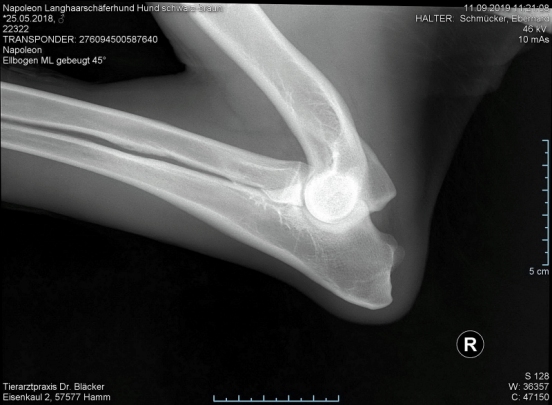

Röntgentermin am 11.09.2019

Hier sind  HD-ED Aufnahmen von unseren “Napoleon von KaTum”   alles Top

Keine HD und kein ED,LÜW ist alles gut